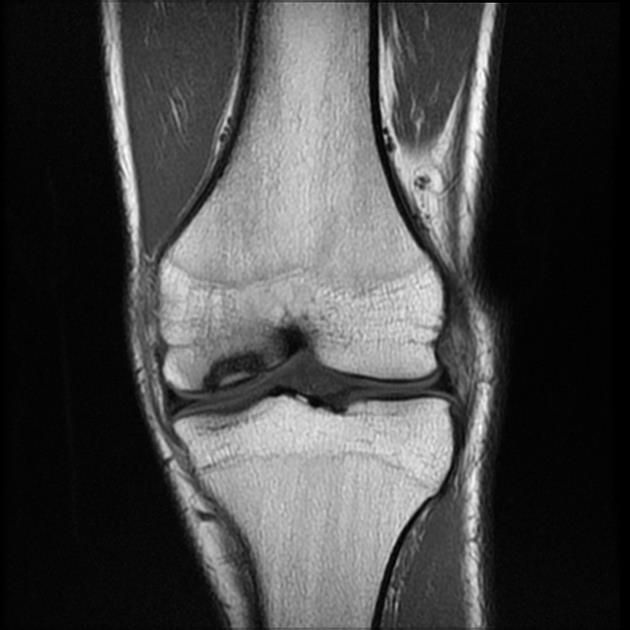

Особенно типичными являются поражения костей — сифилитический остеоходрит и периостит, реже — очаговый остеомиелит. Поражаются симметрично преимущественно длинные трубчатые кости, реже ребра, позвонки и кости пальцев. Сифилитический остеохондрит наблюдается у грудных детей в 97%.

Макроскопически характеризуется наличием на границе эпифиза и мстафиза (хряща и образующейся кости) неровной широкой по сравнению с нормой желтоватой полосы, хорошо выделяющейся .на темно-красном фоне костного мозга и голубоватой ткани хряща (полоса Вегене-ра).

Ранний врожденный сифилис обычно проявляется в течение первых 3 месяцев, жизни. Манифестация включает характерные везикуло-буллезные высыпания или пятнистую медно-красную сыпь на ладонях и подошвах и папулезные поражения вокруг носа и рта и в области подгузников, а также петехиальные высыпания. Часто развиваются генерализованная лимфаденопатия и гепатоспленомегалия. Ребенок может плохо расти и иметь характерные слизисто-гнойные или кровянистые выделения из носа, вызывающие заложенность носа. У некоторых младенцев развивается менингит, хориоидит, гидроцефалия или судороги, у других может развиваться умственная отсталость. В течение первых 8 месяцев, жизни остеохондроз (хондроэпифизит), особенно длинных костей и ребер, может привести к псевдопараличу конечности с характерными радиологическими изменениями в костях.

Сифилис может быть причиной множества различных рентгенологических аномалий длинных костей, включая:

диффузный или локализованый остит;

Остит иногда описывают, как «стержень, диффузно изъеденный молью». Метафизит обычно проявляется, как плотные или блестящие полосы, которые могут чередоваться, придавая вид бутерброда или стебля сельдерея. Знак Вимбергера представляет собой симметричные эрозии верхней берцовой кости, но также могут быть эрозии в метафизе других длинных костей. Было описано избыточное образование каллюса на концах длинных костей. Многие пострадавшие дети имеют более одного из этих показателей.